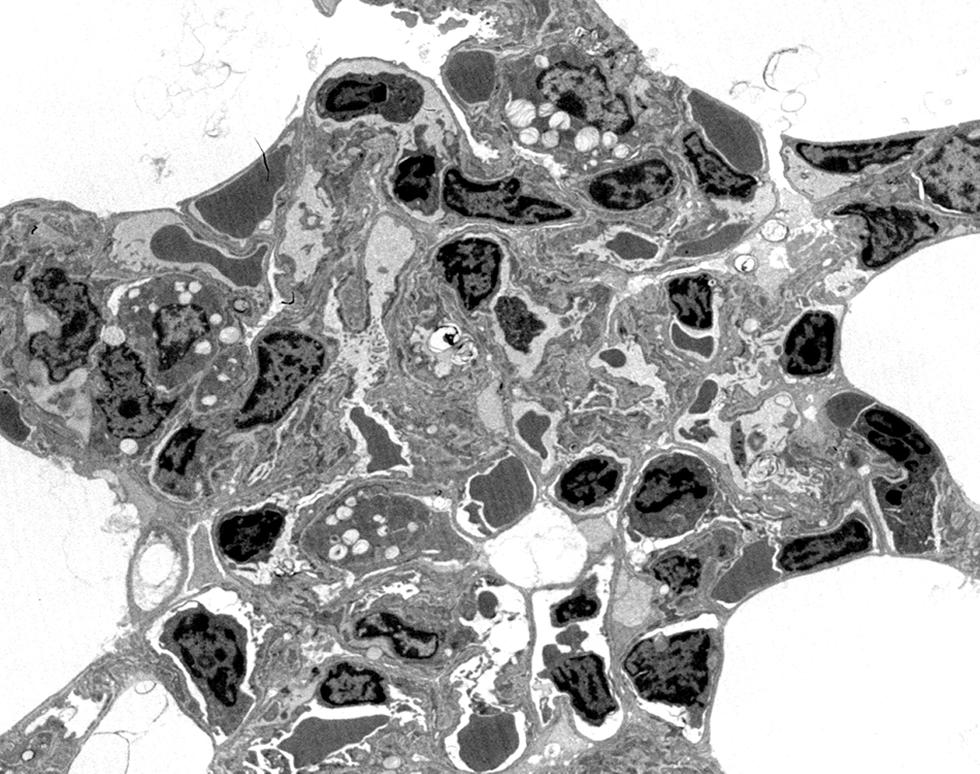

Kearns-Shy syndrome - abnormal mitochondria with paracrystalline inclusions